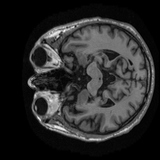

Sample MRI Scans

9 samples

Animated sagittal slices from ADNI-1 subjects across diagnostic groups

CN

CN Subject 1

Animated GIFs show 20 sagittal slices near the brain midline.